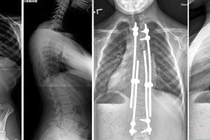

(khoahocdoisong.vn) - Lần đầu tiên Bệnh viện Đa khoa Phú Thọ đã phẫu thuật thành công chỉnh hình cột sống cho trẻ bị vẹo cột sống nặng > 45 độ. Đây là một kĩ thuật phức tạp, thường được triển khai ở bệnh viện tuyến trung ương. Phẫu thuật sớm không chỉ giúp trẻ lấy lại vóc dáng mà còn tránh các biến chứng nguy hiểm về chức năng hô hấp, tim mạch...

(khoahocdoisong.vn) - Biến dạng cột sống rất nặng và cứng nên bắt buộc phải phẫu thuật 2 đường. Phẫu thuật giúp chỉnh cong vẹo, trẻ cao thêm được 11-13cm. Hãy nhận biết các dấu hiệu trẻ bị biến dạng cột sống để cho trẻ đi khám sớm.

Ê-kíp phẫu thuật giải phóng cấu trúc biến dạng, chỉnh trục cột sống, cố định bằng thanh nẹp – vít. Sau mổ, cột sống bệnh nhân được đưa về trục cân đối tự nhiên.